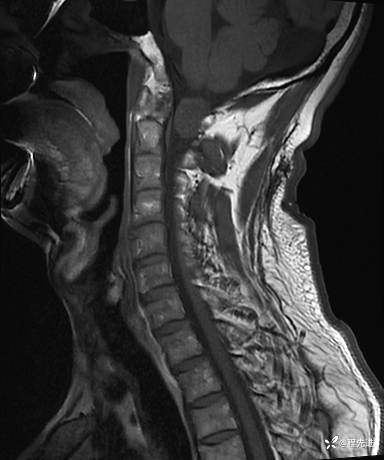

MRI平扫+增强:

T1: